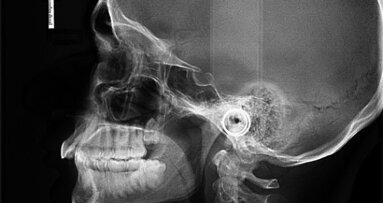

On examination, it was ascertained that she had minimally restored dentition with a large silver amalgam filling in her lower left first molar, and some hypoplastic enamel in her upper right first molar. Her upper left first molar was missing, but there was no residual spacing owing to mesial movement of the second molar. Her lower third molars were unerupted with mesio-angular impaction. She had a thin scalloped gingival biotype.

The patient’s lower incisor teeth had moderate crowding with good positioning of the canines. The upper incisors displayed mild crowding with the mesial edge of the upper right central incisor overlapping the upper left central incisor by 2 mm.